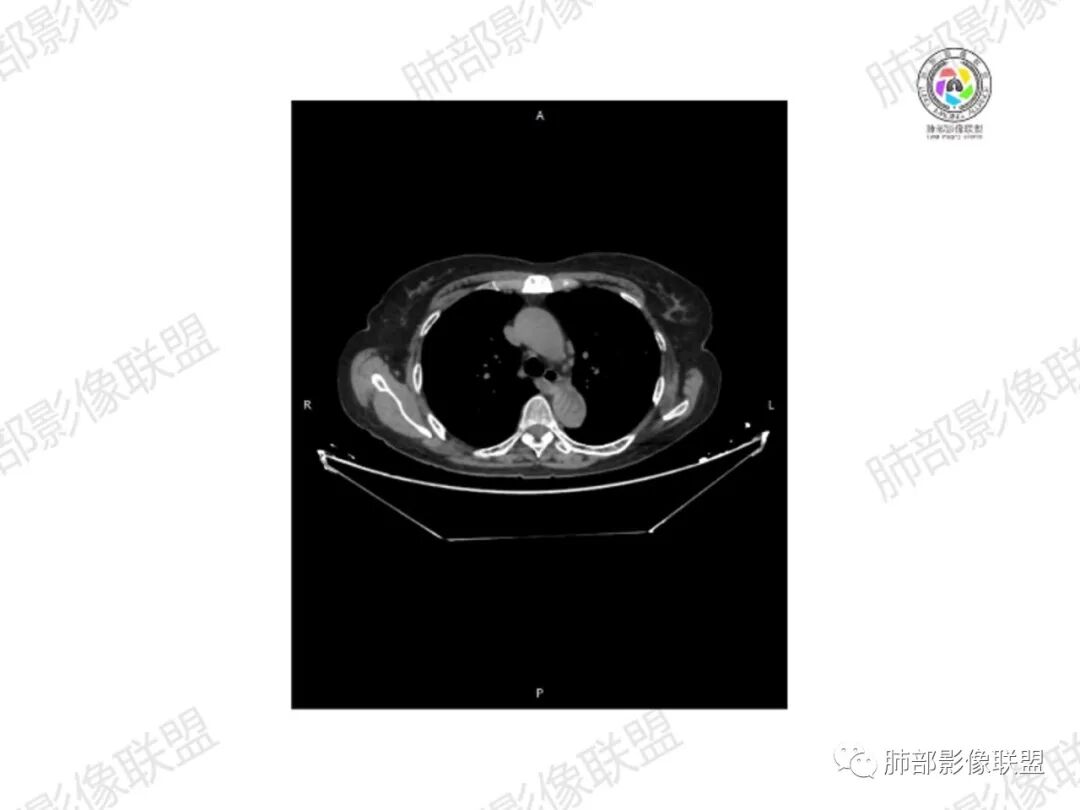

5.双肺多发类圆形结节影,边界清楚,随机分布,其间多见钙化密度影。

6.双肺门及纵隔未见肿大淋巴结。

7.扫描范围内双侧乳腺未见明显块影。

3.双肺病灶符合转移瘤,伴有中央部分钙化者也以骨肉瘤转移较为多见。